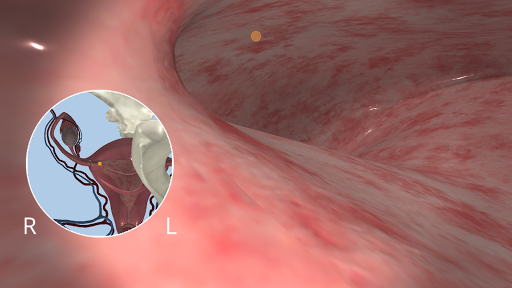

Anatomyou VR est une application mobile éducative qui présente l'anatomie humaine à l'utilisateur d'une manière immersive.

En utilisant la réalité virtuelle, vous serez capable de naviguer le long des structures anatomiques, devenant une partie de l'anatomie humaine: circulatoire, respiratoire, digestive, urinaire, lacrymale et système reproducteur féminin.

Ceci est une version récemment rénovée d'Anatomyou VR. Les fonctionnalités incluent: - Anatomie humaine plus réaliste, améliorant les modèles et les textures. - Meilleure interaction de l'utilisateur en mode VR et en mode plein écran. - Des menus et des images entièrement rénovés permettent une navigation intuitive. - Contenu clinique supplémentaire validé par nos experts. - Les utilisateurs précédents doivent accepter certaines autorisations (GoogleVR SDK). Nous avons mis beaucoup d'efforts dans cette mise à jour, j'espère que vous l'apprécierez!